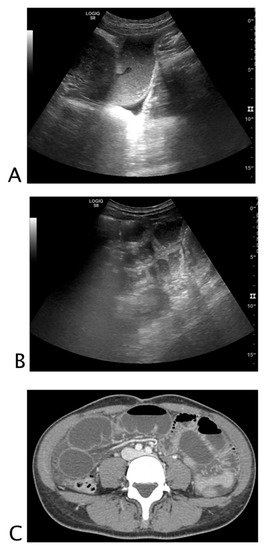

2.1.1. Non-Traumatic Hemoperitoneum

Intraparenchymal Fluid Lesions